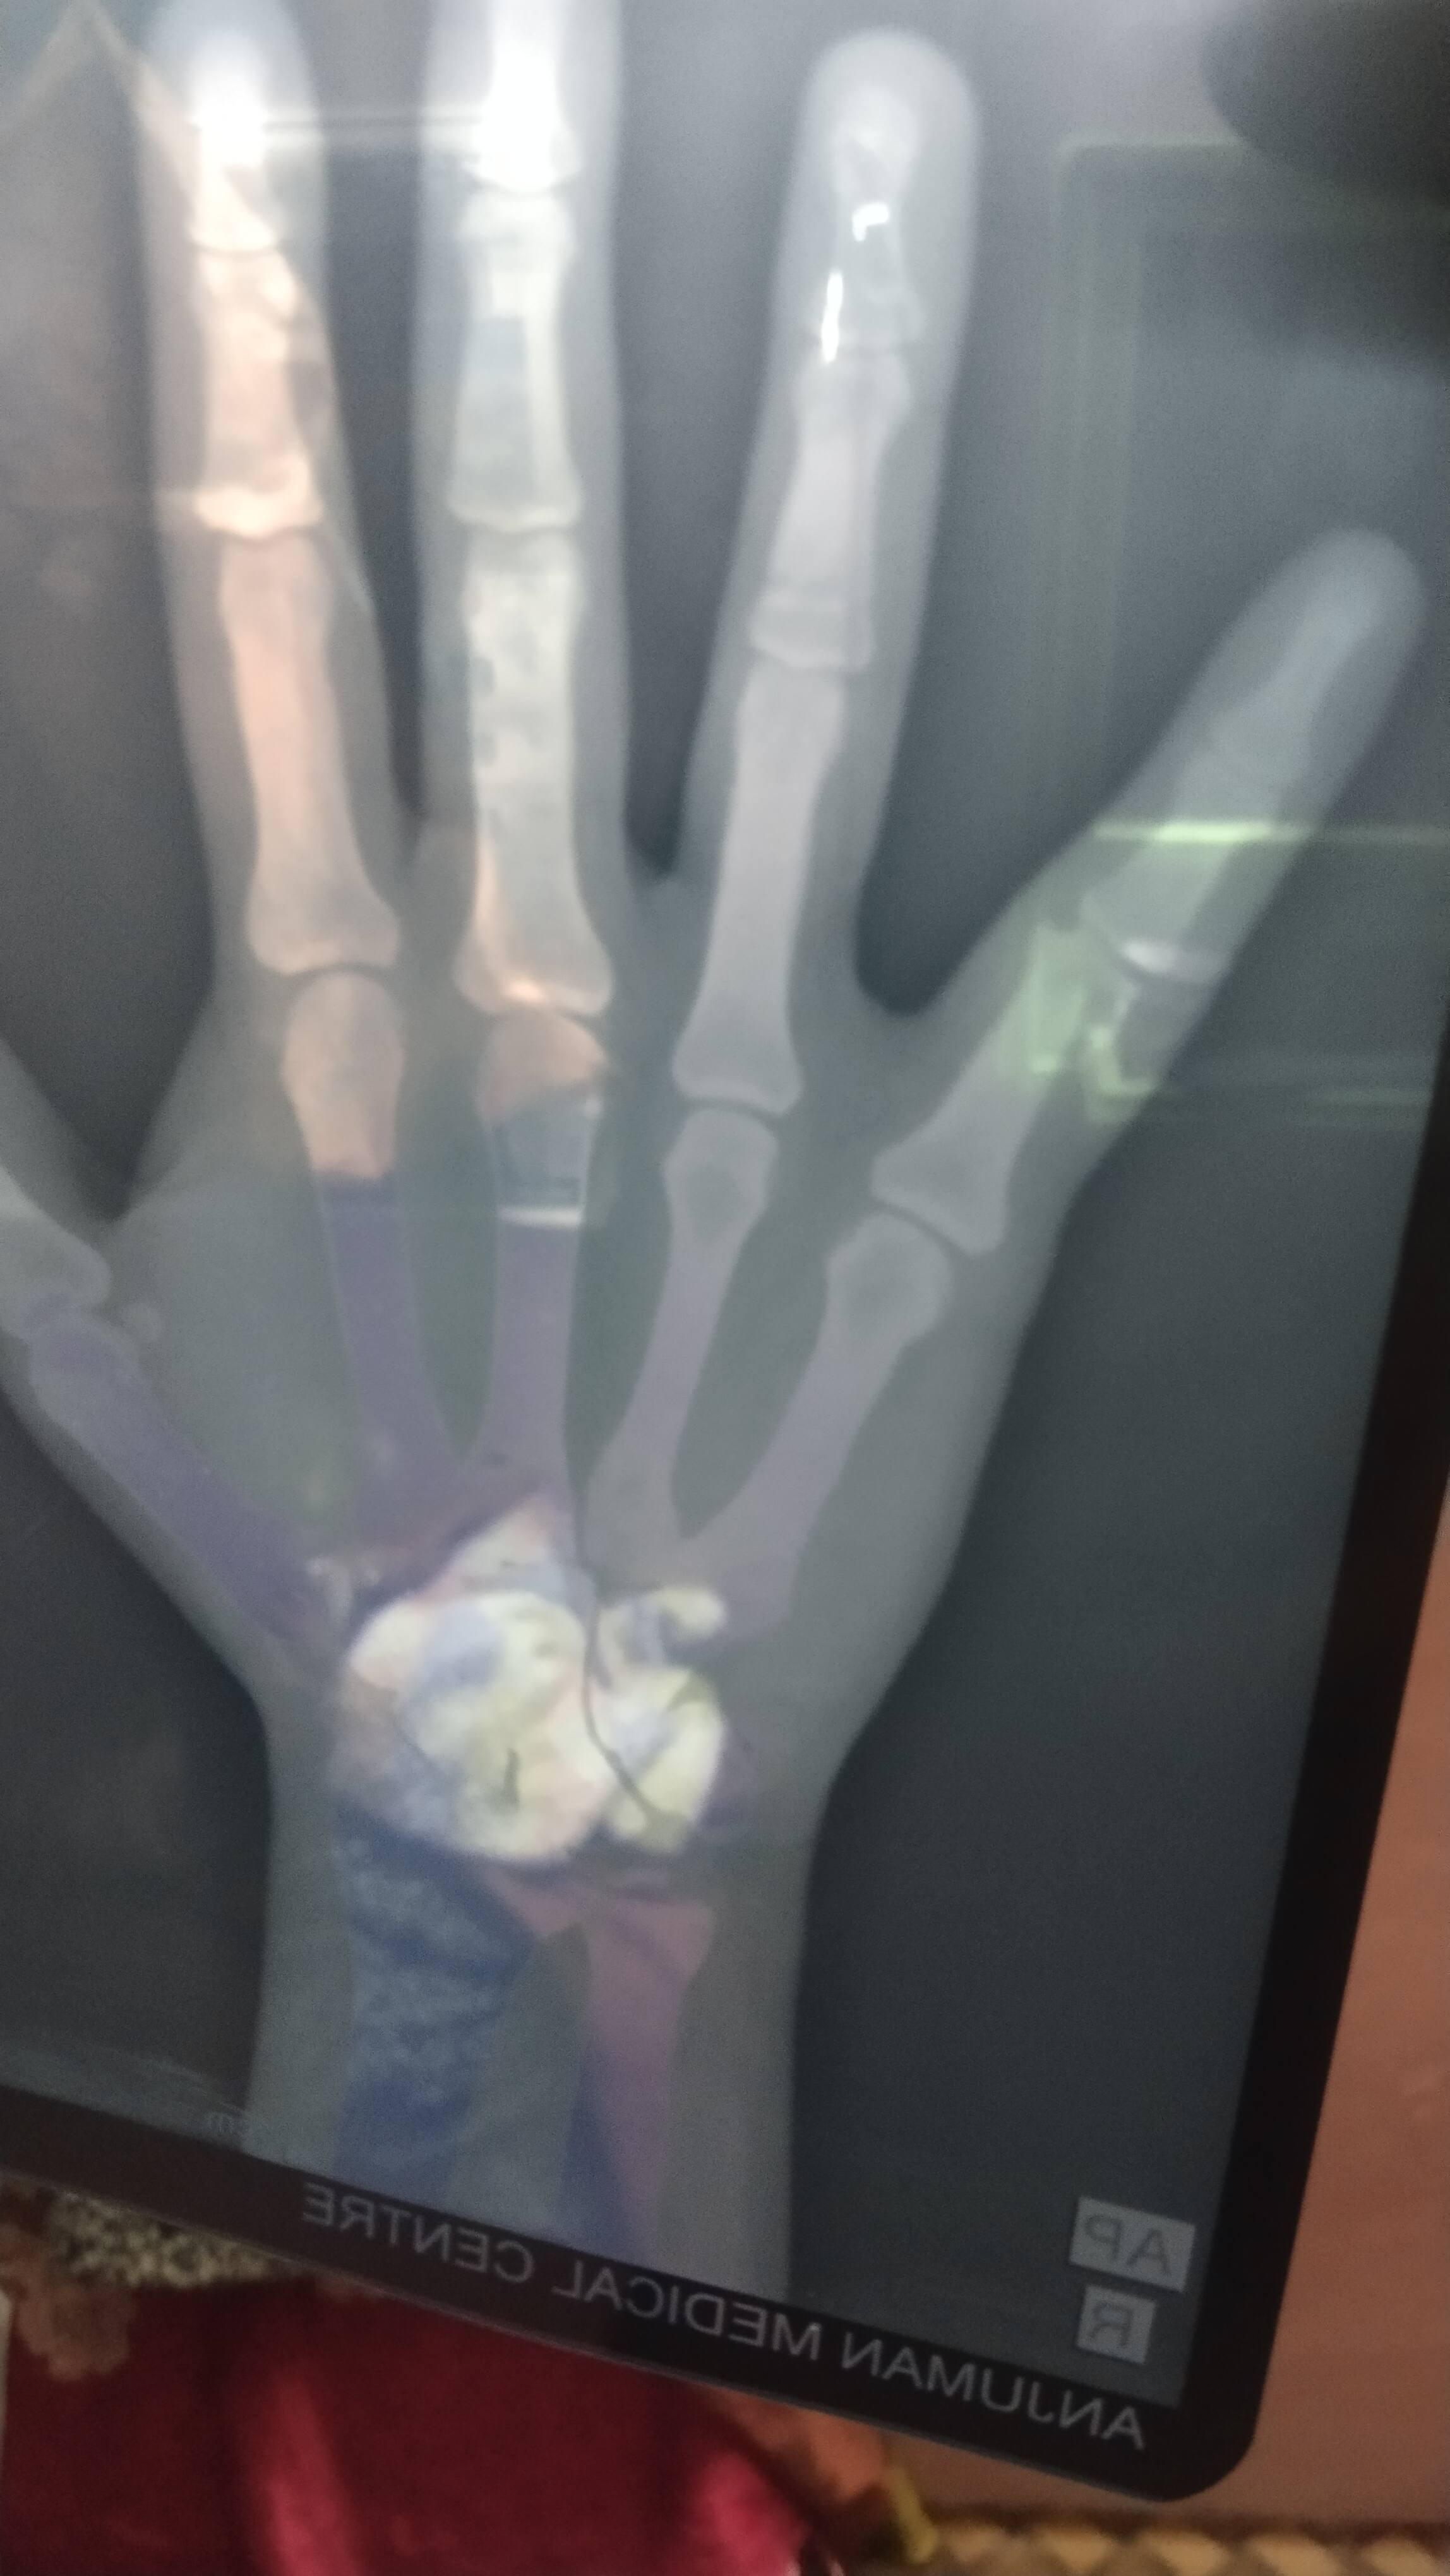

Name: SUDHIR CHOUDHARI

SUDHIR CHOUDHARI

Suggest proper treatment

Dr Naveen Sharma

Isme injury kaise ho gaya tha

Isme plate lagana sahee rahega agar Abhee ka injury hai to . Aur agar time jyada ho gaya to fir to kuch bhee nahee karna hai